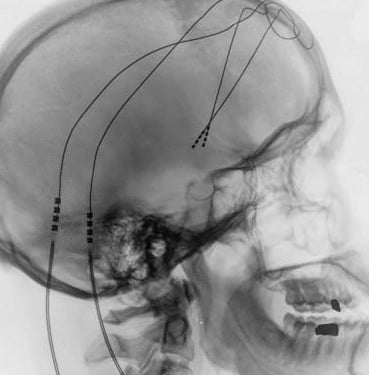

Funktionelle und Epilepsiechirurgie

Chirurgie für fokale Epilepsien

Tiefe Hirnstimulation für Tremor und Parkinson an der Universitätsklinik für Neurochirurgie

Interdisziplinäre Zusammenarbeit mit der Universitätsklinik für Neurologie